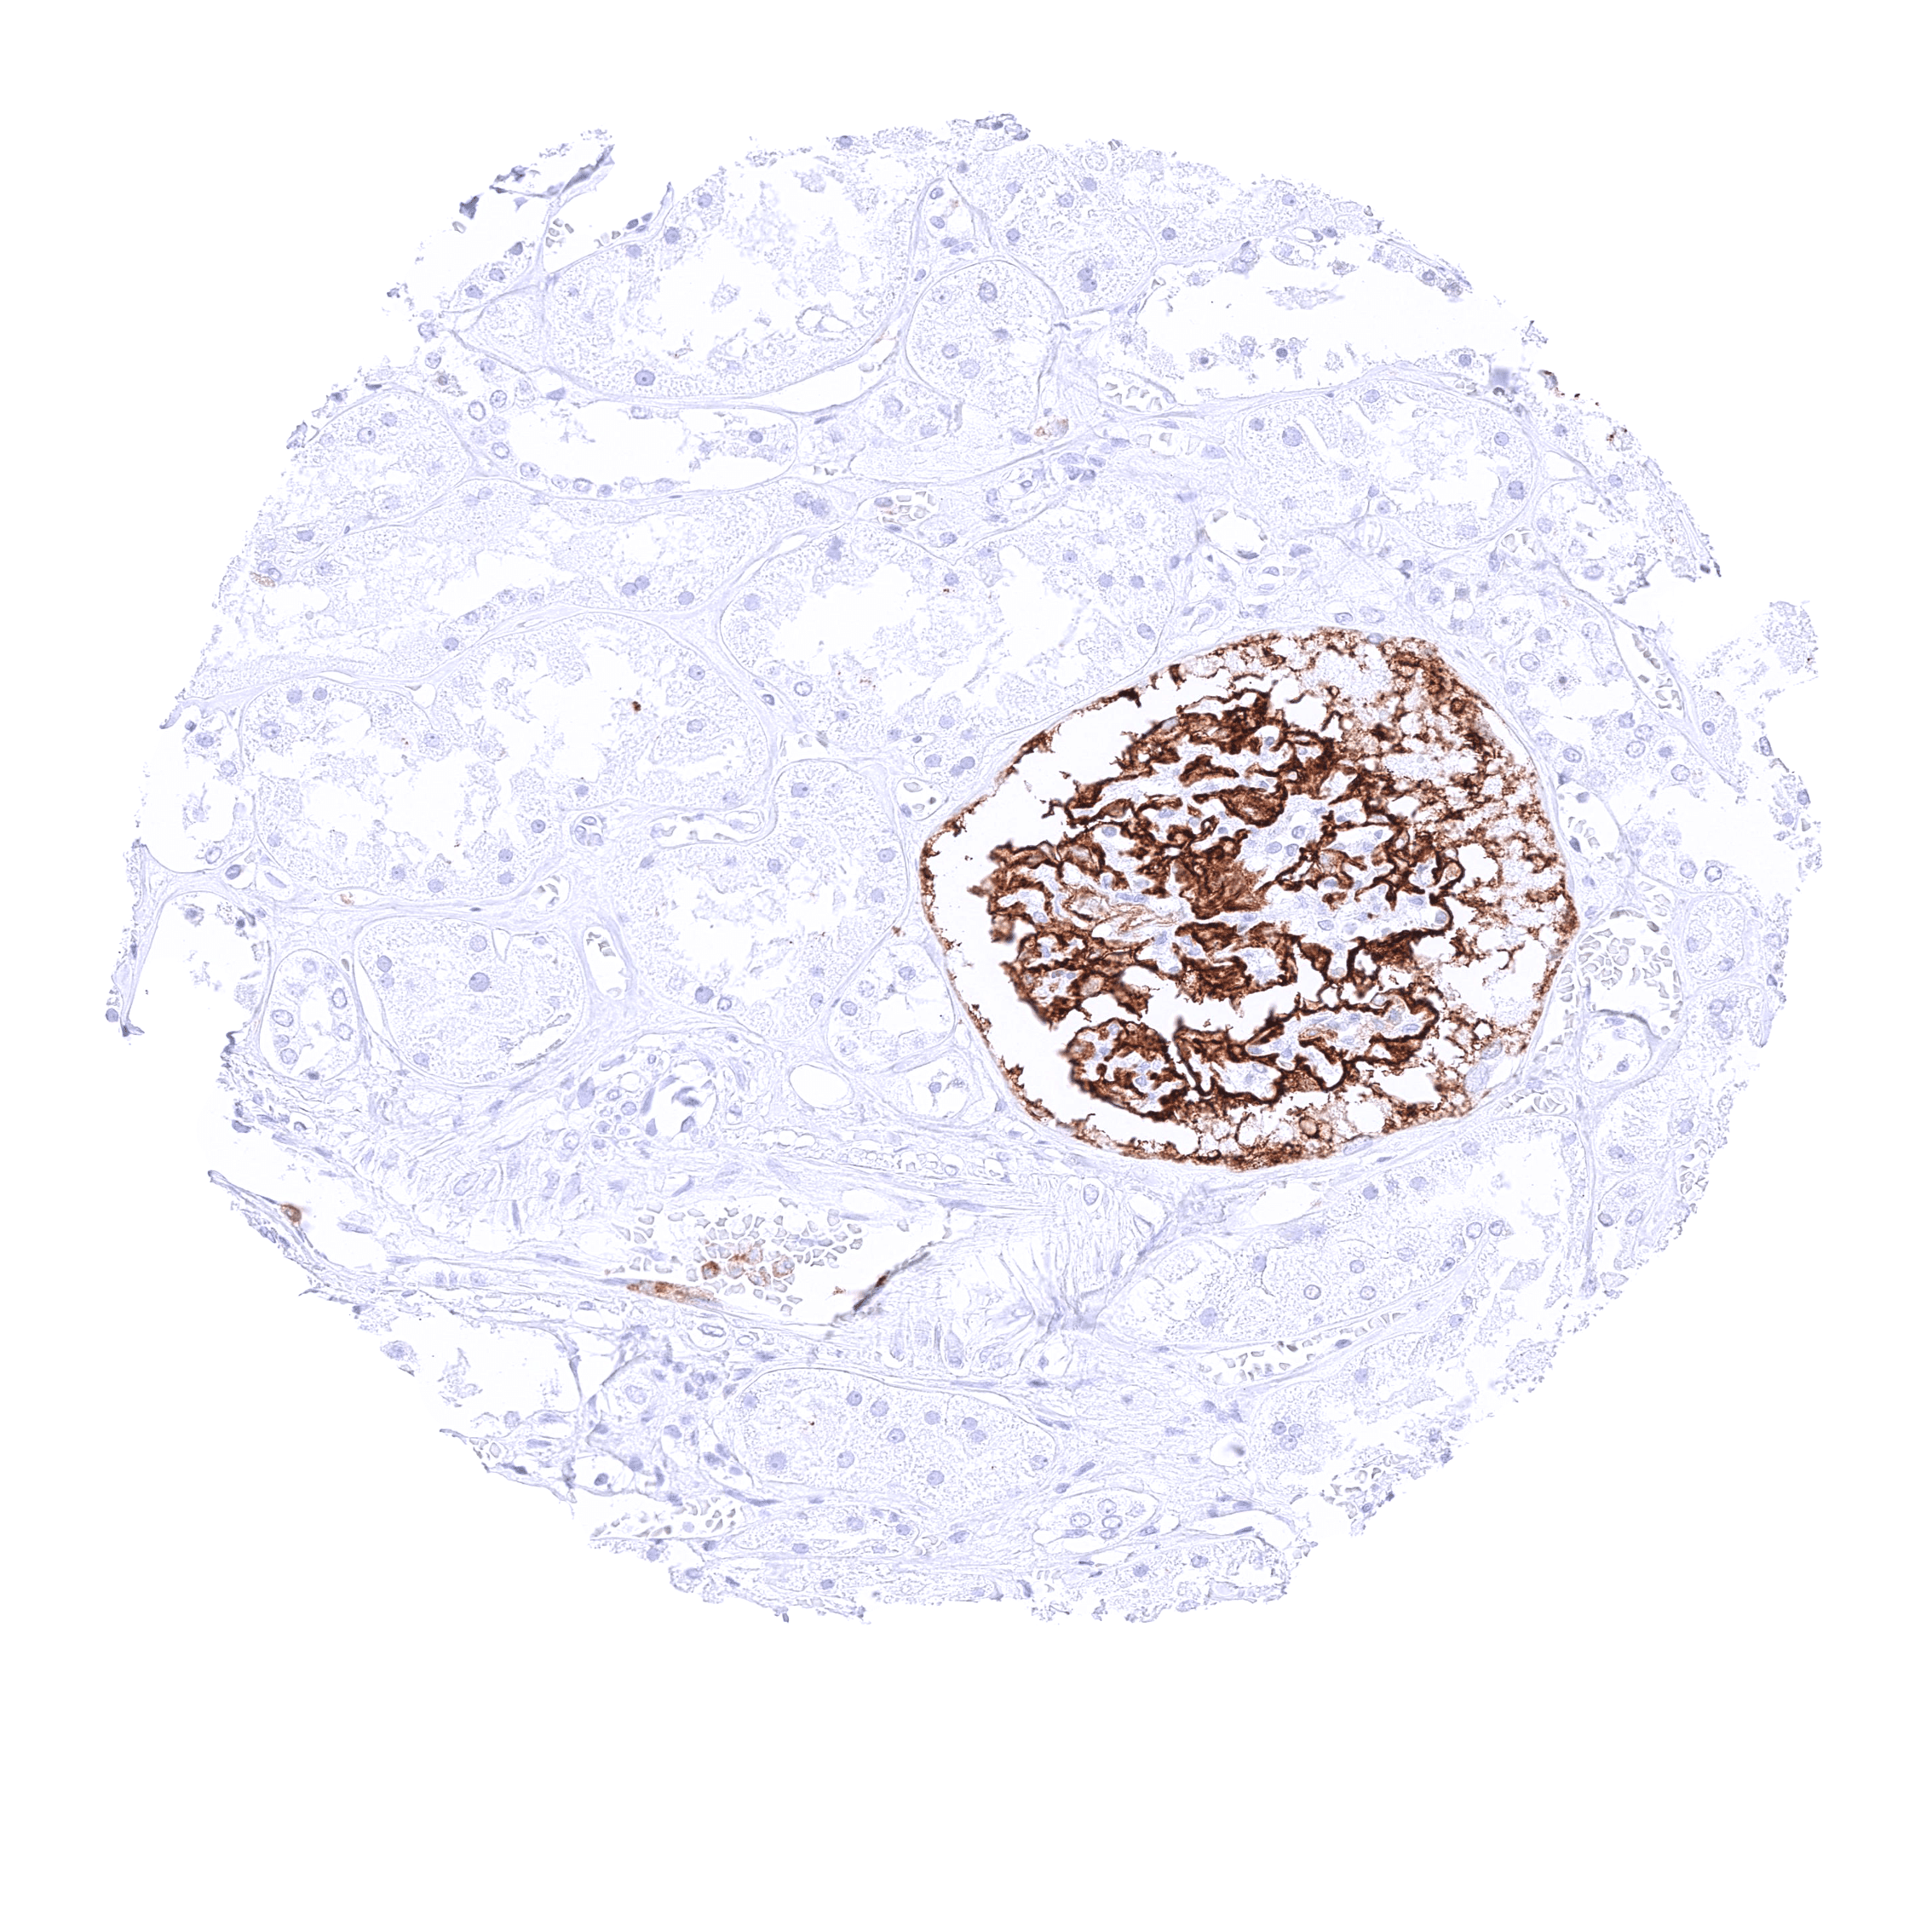

In normal tissues, CD35 is most highly expressed in normal follicular dendritic cells, but it can also be seen on lymphocytes of various types, macrophages, granulocytes, and erythrocytes.

| Lymph node | Strong membranous CD35 staining of follicular dendritic cells and of a subset of lymphocytes. | |

| Spleen | Strong membranous CD35 staining of most cells in the white pulpa. | |

| Tonsil | Strong membranous CD35 staining of follicular dendritic cells and of a subset of lymphocytes. The squamous epithelium is CD35 negative. | |